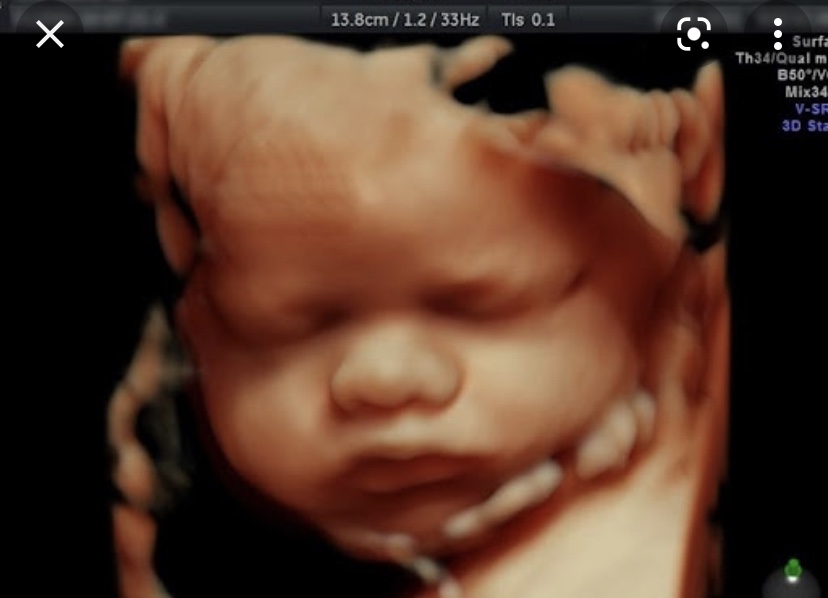

Девочки, поделитесь, кто делал 3д узи?

Не пожалели ли? Стоит ли того?

Дааа,делала в 32 недели,не пожалела денег,такие эмоции и сын родился один в один что на фото

С 16 недели беру 3д. Ни разу не пожалела.